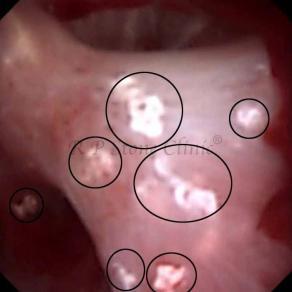

Kidney stone is a solid mass of CRYSTALS. It is the process of crystallization which initiates the formation of kidney stones. This happens in nephrons or units of kidney. Once a small crystal is formed, it can both grow & unite with other crystals leading to the formation of small concretion which eventually forms a stone. Once these large crystals detach from the collecting ducts, the process of stone formation starts in the renal collecting system. A recurrent kidney stone former is advised to know a little bit about something known as Randall’s plaque. Alexander Randall discovered plaques on the renal papillae eight decades back based on examination of 1154 pairs of autopsied Kidneys. He described these renal papillary lesions as cream colored or milk patch areas composed of calcium phosphate & calcium carbonate. These plaques could act as NIDUS for formation of KIDNEY STONE. Calcium Oxalate stone can form on this nidus & then detaches from this plaque to become a free floating stone in the collecting system of kidney

These images are taken as snap shots from the video recording of RIRS Surgery done at our hospital. These are Randall’s Plaques seen with Digital FLEX XC & Digital FLEX XC S. The cream or whitish patches are seen on the tips of RENAL PAPILLAE as seen in images below.

Randall’s Plaques may lead to the formation of Stones.

Those kidney stone patients who have Randall’s Plaques in their kidneys are more likely to form stones again (Recurrent Stones).

Stone Patients in whom Randall’s Plaques are detected at the time of RIRS Surgery should undergo regular ultrasound examination for early detection of stones.

Patients of Stones with Randall’s Plaques in their Kidneys should drink plenty of fluids in addition to Orange Juice & Lemonade.